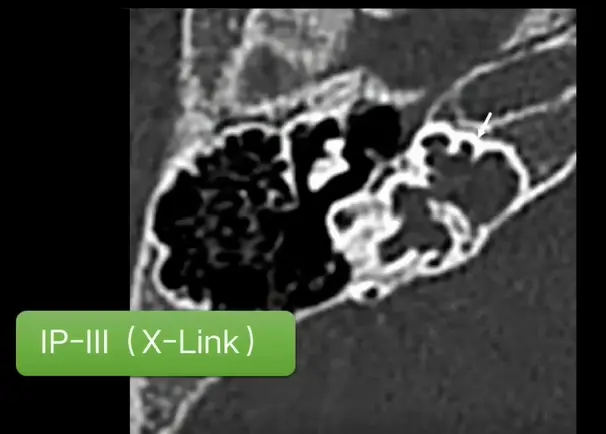

IP-III

IP-Ⅲ是耳蜗植入难度非常高的一种内耳畸形,其耳蜗与内听道间无分割,耳蜗内无蜗轴,易将电极植入至内听道内。若植入内听道,则不能感知声音还会出现面部抽搐,须进行二次手术。